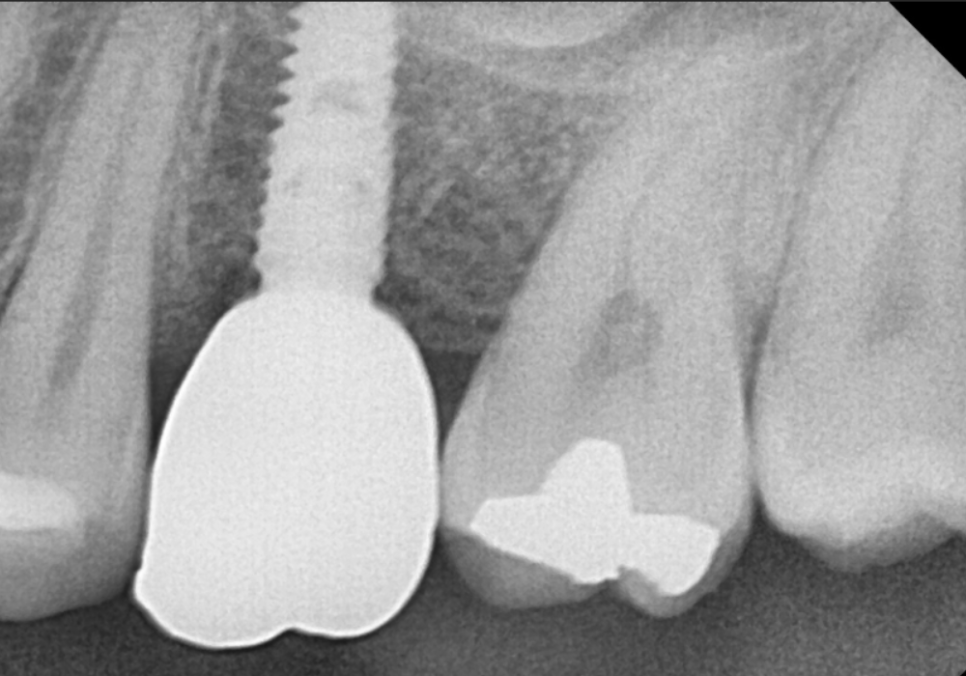

상실되었던 어금니 임플란트 역시

정확한 위치에 식립되어 튼튼하게 완성되었답니다.

260404